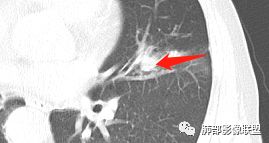

影像学特点:肺气肿背景下在大概一年的时间里出现了一个光滑的小结节,因为图像给的不是太薄,与支气管的关系判断不清,从结节周围出现斑片状炎症来判断,应该考虑结节位于支气管内,周围是阻塞性炎症,这样比较容易解释咯血

纵隔窗上似乎结节内可见点状高密度影,同时没有明显肿大淋巴结

左肺上叶光滑结节影 似乎与支气管没有关系  ,给的纵隔窗病灶中心似乎点状钙化  病灶旁有更小结节,与上一年片比较 结节增大明显  考虑恶性 类癌可能

后头看前片似乎当时腔内壁稍增厚一点